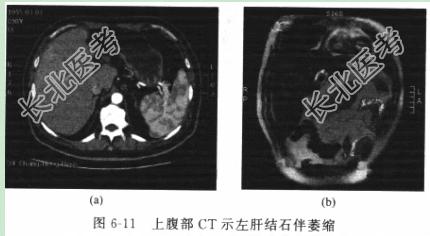

- [材料题] 患者男性,60岁,因“反复剑突下疼痛伴畏寒、发热20余年”入院。20余年前开始反复出现剑突下疼痛,伴有畏寒、发热不适,经抗感染治疗后症状缓解,上述症状反复发作。10年前行“腹腔镜胆囊切除术”,5年前在外院行超声引导下“肝脓肿引流术”。患者一般情况尚可,平素进食欠佳,不敢吃油腻食物。体格检查体温(T)36.6℃,呼吸(R)20次/分,脉搏(P)76次/分,血压(BP)115/80mmHg。神志清楚,体型消瘦。皮肤、黏膜无明显黄染。腹平软,可见腔镜手术瘢痕,剑突下偏右压痛、叩击痛,余未及阳性体征。辅助检查血常规示WBC15.3×10⁹/L,N81.2%,Hb113g/L,总胆红素(TBIL)17.1μmol/L,直接胆红素(DBIL)5.6μmol/L,其他肝肾功能指标和病毒检测、凝血功能、血气分析、肿瘤标记物等结果均未见明显异常。B超:提示肝左外叶胆管扩张,见多个强光团伴声影,胆总管上段内径18mm,可见充满结石,未见胆囊。CT(图6-11):左肝外叶呈蜂窝样改变,可见高密度结石影,局部胆管扩张。MRCP(图6-12):胆总管结石,胆总管上段扩张,左肝萎缩。